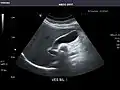

Abdominal ultrasonography (also called abdominal ultrasound imaging or abdominal sonography) is a form of medical ultrasonography (medical application of ultrasound technology) to visualise abdominal anatomical structures. It uses transmission and reflection of ultrasound waves to visualise internal organs through the abdominal wall (with the help of gel, which helps transmission of the sound waves). For this reason, the procedure is also called a transabdominal ultrasound, in contrast to endoscopic ultrasound, the latter combining ultrasound with endoscopy through visualize internal structures from within hollow organs.

Abdominal ultrasound can be used to diagnose abnormalities in various internal organs, such as the kidneys,[1] liver, gallbladder, pancreas, spleen and abdominal aorta. If Doppler ultrasonography is added, the blood flow inside blood vessels can be evaluated as well (for example, to look for renal artery stenosis). It is commonly used to examine the uterus and fetus during pregnancy; this is called obstetric ultrasonography.[2][3]

Abdominal ultrasound is commonly used in the setting of abdominal pain or an acute abdomen (sudden and/or severe abdominal pain syndrome in which surgical intervention might be necessary), in which it can diagnose appendicitis or cholecystitis.